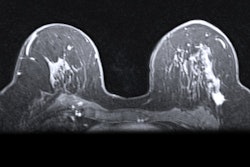

The company's SuiteHeart version 5.0.2 has deep-learning algorithms designed to identify and segment the superior and inferior vena cava; the ascending and descending aorta; and the main, left, and right pulmonary arteries. Doing so can speed up heart assessment, according to NeoSoft.